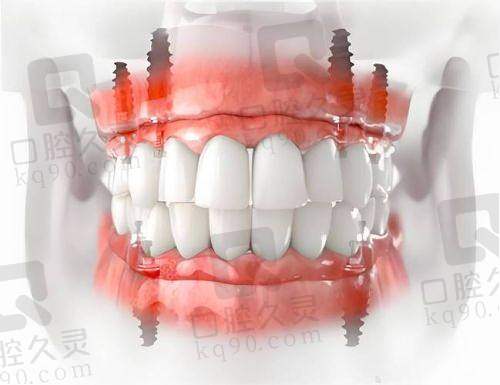

精良的技术设备:南昌虹桥口腔医院引进了国内外精良的种植牙技术和设备,如数字化口腔扫描系统、种植导航系统等。这些设备能够严谨地获取患者的口腔数据,为种植牙手术提供更精细的指导,提高手术的成功几率和安心性。